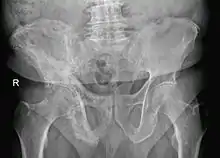

Paget's disease of bone

Paget's disease of bone (commonly known as Paget's disease or, historically, osteitis deformans) is a condition involving cellular remodeling and deformity of one or more bones. The affected bones show signs of dysregulated bone remodeling at the microscopic level, specifically excessive bone breakdown and subsequent disorganized new bone formation.[1] These structural changes cause the bone to weaken, which may result in deformity, pain, fracture or arthritis of associated joints.[1]

The exact cause is unknown, although leading theories indicate both genetic and acquired factors (see Causes). Paget's disease may affect any one or several bones of the body (most commonly pelvis, tibia, femur, lumbar vertebrae, and skull), but never the entire skeleton,[1][2][3] and does not spread from bone to bone.[4] Rarely, a bone affected by Paget's disease can transform into a malignant bone cancer.

- Pagetic bone has a characteristic appearance on X-rays. A skeletal survey is therefore indicated.

- Bone scans are useful in determining the extent and activity of the condition. If a bone scan suggests Paget's disease, the affected bone(s) should be X-rayed to confirm the diagnosis.